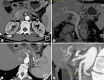

We describe a case of clinical benefit and partial response with gemcitabine and oxaliplatin (GEMOX) in a young patient with ovarian metastasis from cystadenocarcinoma of the pancreas. A young woman complained of abdominal pain and constipation. Computed tomography (CT) and magnetic resonance imaging scans disclosed two bilateral ovarian masses with pancreatic extension. She underwent bilateral ovarian and womb resection. During surgery peritoneal carcinosis, a pancreatic mass and multiple abdominal lesions were found. The final diagnosis was mucinous pancreatic cystadenocarcinoma with ovarian and peritoneal metastases. She started chemotherapy with GEMOX (gemcitabine 1,000 mg/m(2)/d1 and oxaliplatin 100 mg/m(2)/d2 every 2 weeks). After 12 cycles of chemotherapy a CT scan showed reduction of the pancreatic mass. She underwent distal pancreatic resection, regional lymphadenectomy and splenectomy. Pathologic examination documented prominent fibrous tissue and few neoplastic cells with mucin-filled cytoplasm. Chemotherapy was continued with gemcitabine as adjuvant treatment for another 3 cycles. There is currently no evidence of disease. As reported in the literature, GEMOX is associated with an improvement in progression-free survival and clinical benefit in patients with advanced pancreatic cancer. This is an interesting case in whom GEMOX transformed inoperable pancreatic cancer into a resectable tumor.